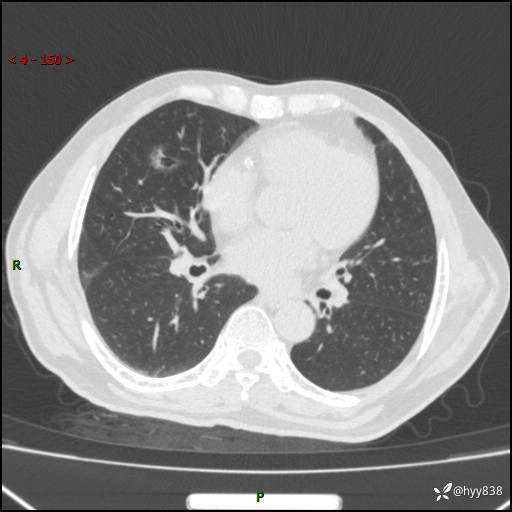

现病史:患者4月前无明显诱因后背正中间疼痛,间断阵痛,无低热、咳嗽,盗汗、咯血、胸痛、喘气等不适,2024-2-25当地市第二人民医院胸部CT提示“1.双肺感染病变;2.右肺中叶结节灶;3.双肺肺气肿并肺大泡4.主动脉及冠脉硬化,今为求明显结节性质遂来我院门诊就诊,门诊以“肺占位”收治入院。 起病以来,患者精神饮食睡眠一般,大小便正常,体力体重无明细变化。

胸部CT平扫(2024.2)